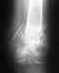

Re: Перелом верхней трети кости бедра

Для 6-летнего такое положение приемлемо, с с дальнейшим ростом остаточная деформация исправится. "MTP № 10 2 курса" избыточна.